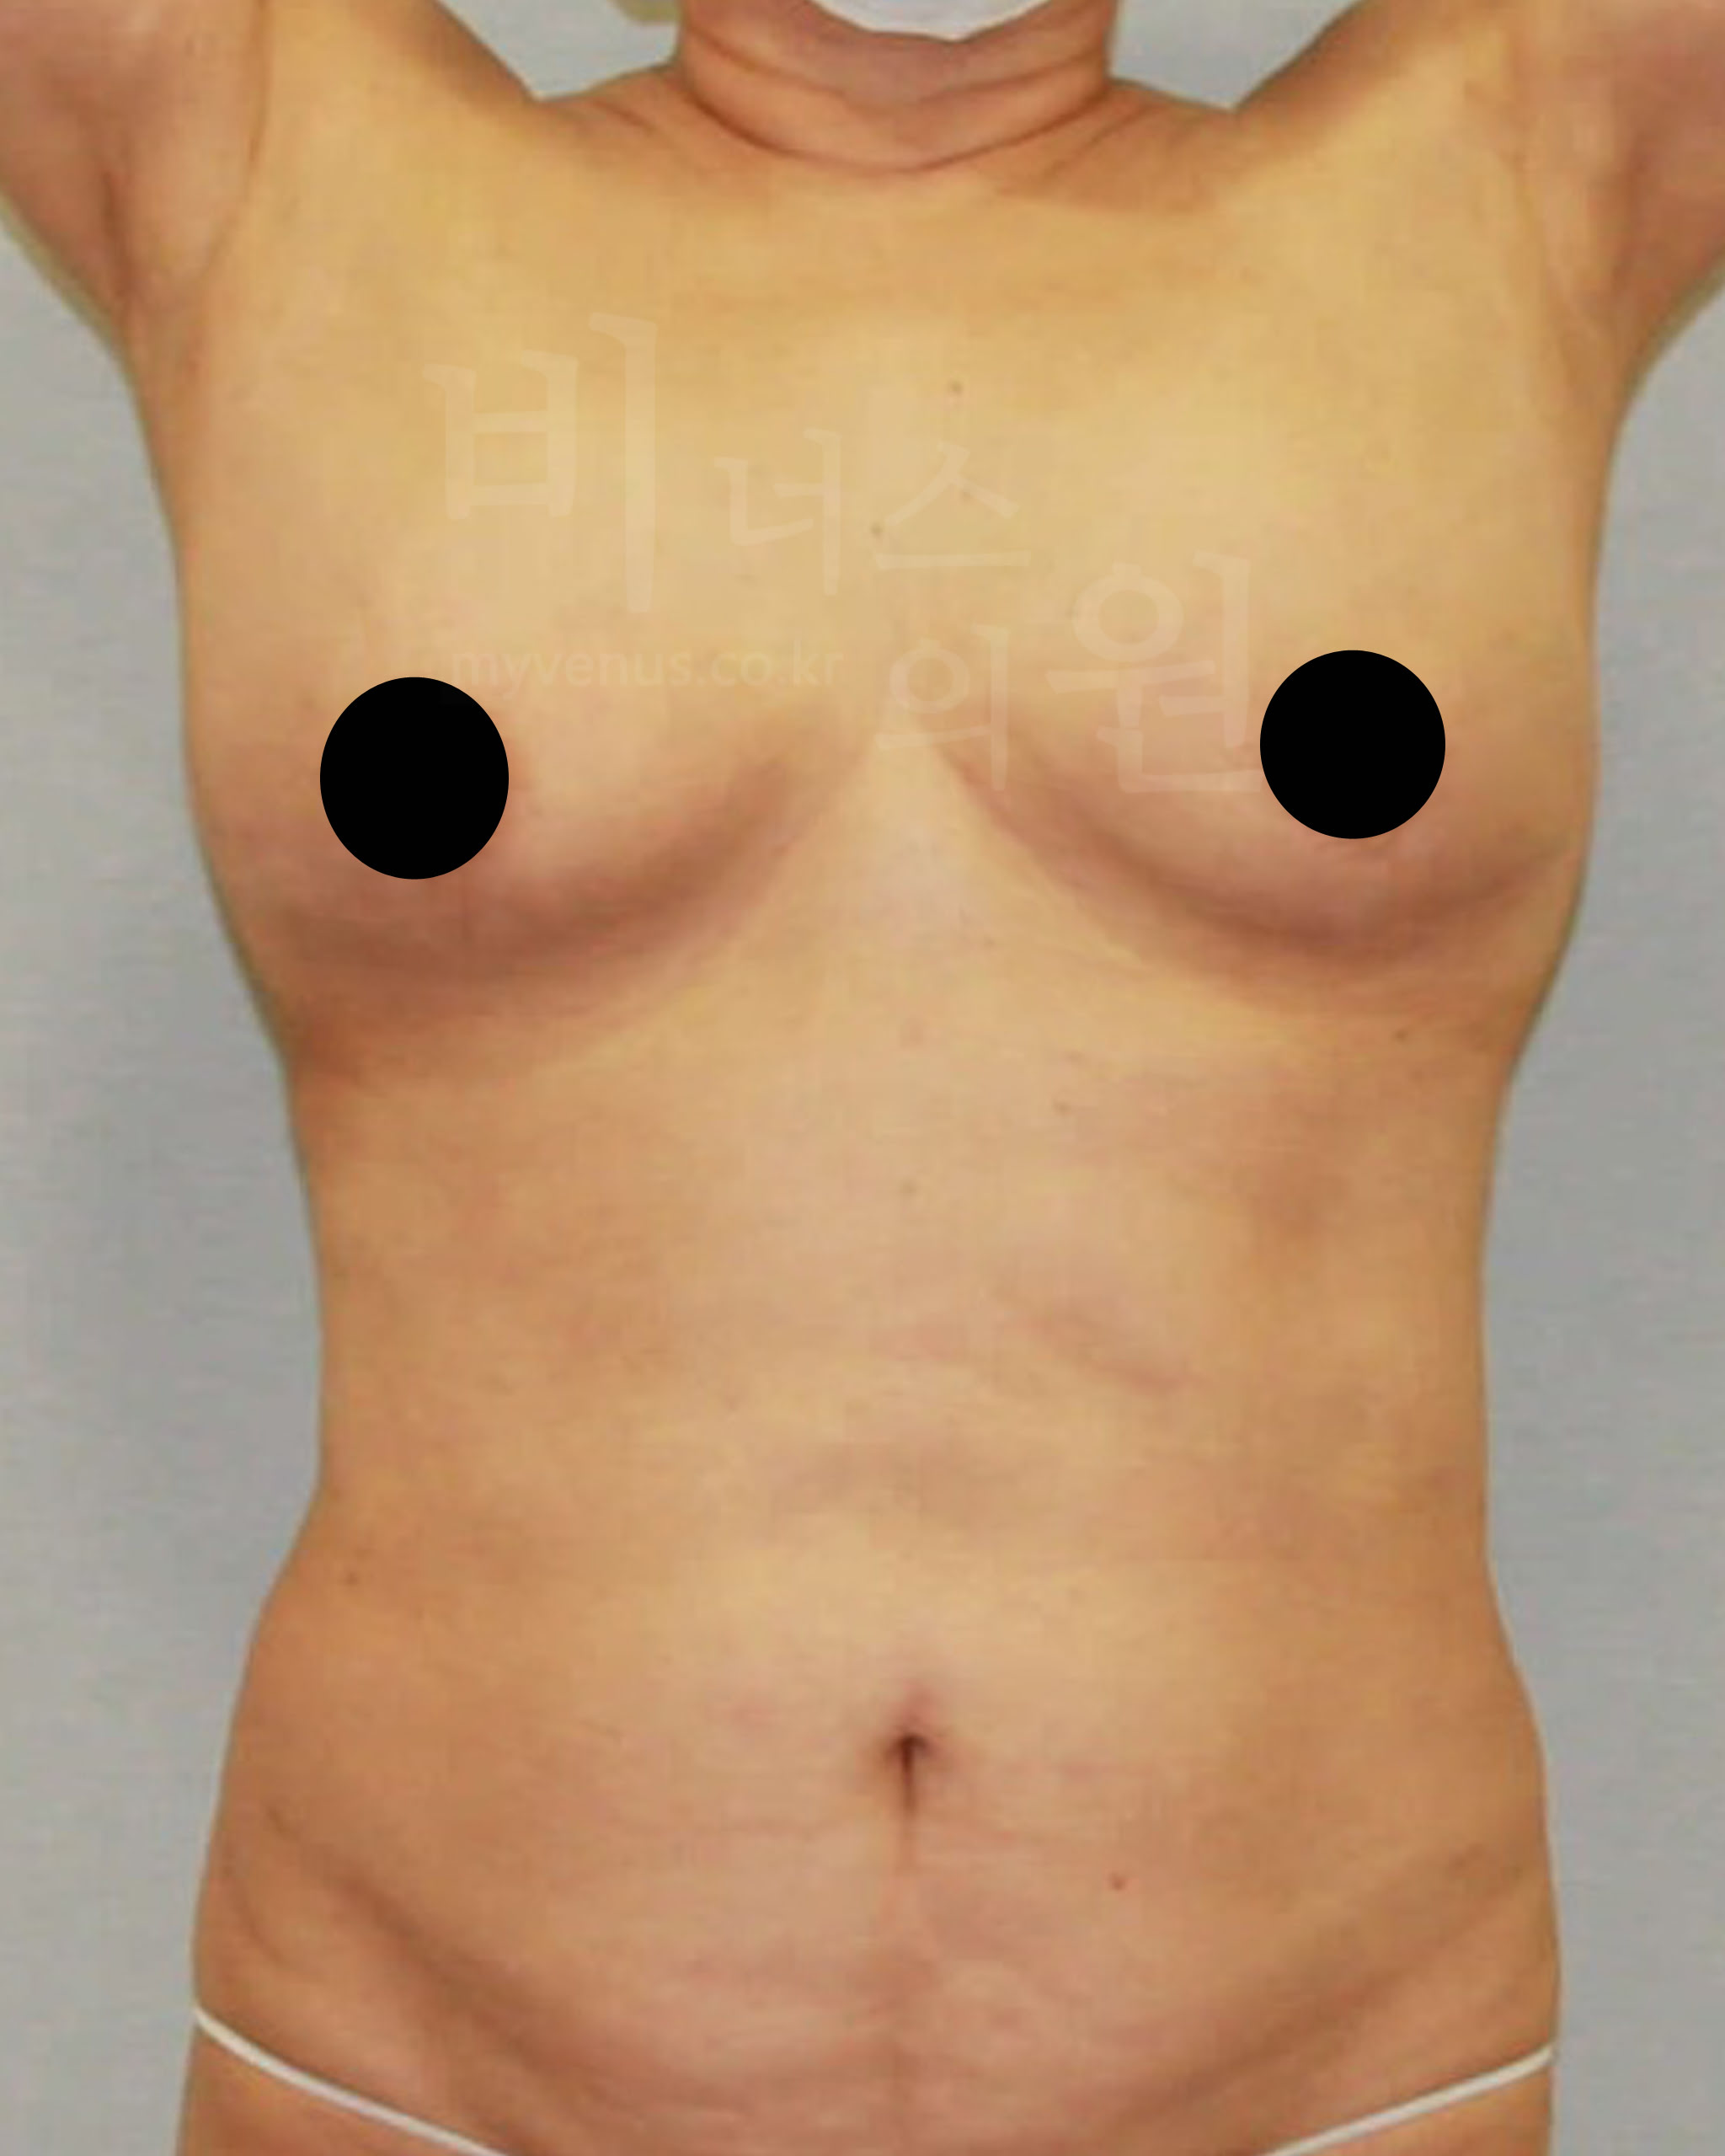

가슴축소 지방흡입 전 사진

가슴이 처져 길게 늘어진 모습

가슴축소 지방흡입 후 사진

늘어진 가슴이 리프팅 되어 업이 된 모습

처짐의 개선으로 가슴과 젖꼭지가 위로 업이 되면서 봉긋하게 변화하였어요. 사이즈 감소와 가슴 선의 길이가 짧게 감소하였으며 유방의 부피가 작아져 가벼워 보여요.

가슴축소 지방흡입 전 사진

유방 옆구리에 지방이 많은 모습

가슴축소 지방흡입 후 사진

유방 옆구리와 주변 부위에 군살이 제거된 모습

부천지방흡입의 가슴축소는 기계를 사용하지 않고 의사의 손 핸들링으로 지방을 흡입하는 수술 방법으로 특수 제작된 마이크로캐뉼라를 이용하여 깊이를 정확하게 판단하고 피부 표면의 상태를 투시하여 시술하기 때문에 일반적인 기계지방흡입에 비해 안전하고 결과 또한 좋아요.

수술 부위 - 가슴 축소, 부유방, 겨드랑이, 유방 옆구리 지방흡입